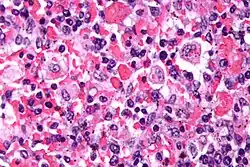

| Micrograph showing red blood cells within macrophages. H&E stain. | |

The blood count typically shows decreased numbers of blood cells—including a decreased number of circulating red blood cells, white blood cells, and platelets. The bone marrow may show hemophagocytosis. The liver function tests are usually elevated. A low level of the protein albumin in the blood is common.

Bone marrow biopsy shows histiocytosis.[20]

- Haemophagocytosis in the bone marrow, spleen or lymph nodes